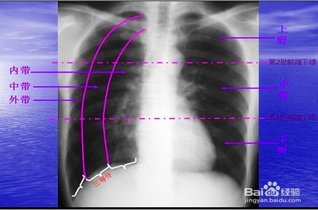

胸片怎么看

学会看胸片是临床医生必备的技能之一,首先,看胸壁的X线表现,观察胸壁软组织有大的肿块,有皮下积液、积气,同时观察肋骨的连续性是否有中断,这是肋骨骨折的X线征象...73227人收听

在临床上胸部X光片检查是常用的一种检查方法,它是利用X线产生图像,从而观察胸部的病变。胸片的观察需要按一定的顺序,一般可以按照从上往下的顺序,观察双肺上叶...1人收听